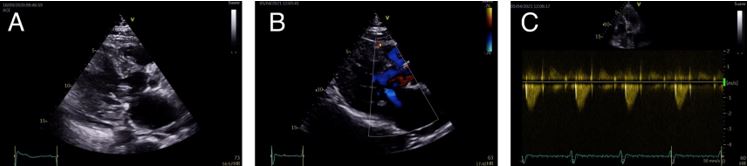

Alcohol septal ablation was performed without complications and the haemodynamic status improved with a sharp decrease in the maximum LVOT gradient (60 mmHg), and a slight elevation of blood pressure. Hours after the ablation procedure, the patient developed a complete atrioventricular block. A dual-chamber pacemaker was implanted via the left axillary route, placing the ventricular electrode in the right ventricular apex.

Fig 3 - Clinical Case - hypertrophic cardiomyopathy.jpg